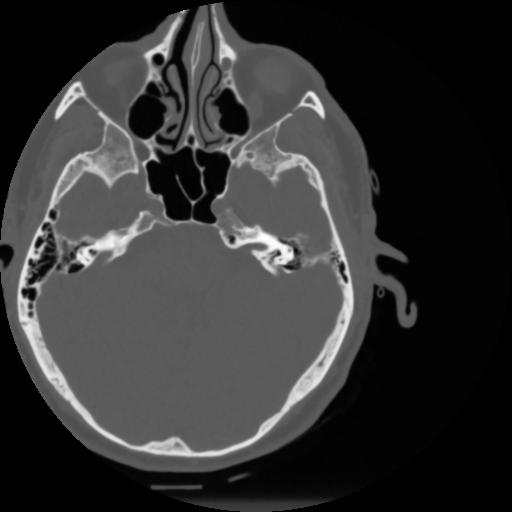

4 CEREBRO,,Vol,0.5,CEREBRO,,